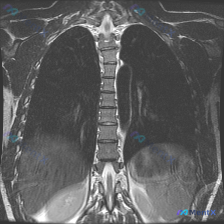

- 影像核心发现:双侧下肺野/膈顶部T2高信号,呈典型“半月征”,符合双侧胸腔积液;纵隔居中,无明显肿大淋巴结,肺野内没看到明确实变或占位,胸壁软组织、肋骨及胸椎骨髓信号看起来均匀。

- 但有个有意思的点:最初的观察诉求是“Scoliosis(脊柱侧弯)”,影像宏观描述提了“胸廓对称”,但分析里也指出——不能仅凭“骨髓信号均匀”就直接否定骨骼畸形或侧弯的存在。